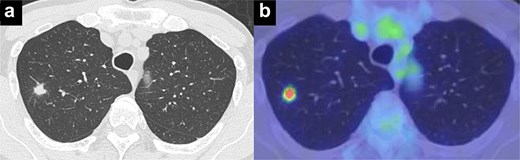

A man in his 70s presented for evaluation of a lung nodule on follow-up computed tomography (CT) 1 year postsurgery for early gastric adenocarcinoma. He had a history of heavy smoking (1.5 packs per day for 50 years) and had quit 1 year prior. CT revealed a 1.5 cm irregularly marginated solid nodule in the apical segment of the right upper lobe (Fig. 1a). Positron emission tomography (PET) revealed a maximum standard uptake value of 4.6 on the nodule (Fig. 1b). PET and brain magnetic resonance imaging revealed no metastases. All tested serum tumour marker values were within normal ranges. CT revealed emphysema of the lung. Pulmonary function tests indicated a forced expiratory volume in 1 s (FEV1.0) of 2130 ml and an FEV1.0/forced vital capacity ratio (FEV1.0%) of 65.3%. Bronchoscopic biopsy was not performed owing to difficulty in obtaining an informative specimen, and the lesion was suspected to be primary lung cancer. Although the size and location of the nodule met the criteria for intentional limited resection to treat lung cancer [3], lobectomy was considered more appropriate than apical segmentectomy for a sufficient margin and tolerable pulmonary function.